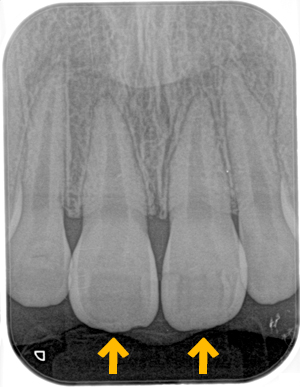

歯周疾患検診

歯の状態を視診で確認し、

はぐきの状態を専用の器具を用いて診査していきます。

歯肉の炎症の有無についても確認していきます。